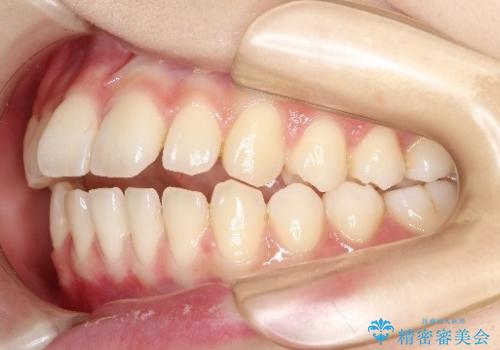

初診時の歯並びの状態としては、上下前歯が噛んでいない開口という状態であり、前歯を中心に上下とも歯の間に隙間がある状態でした。

抜歯は行わずマウスピース治療による主訴の改善を計画しました。